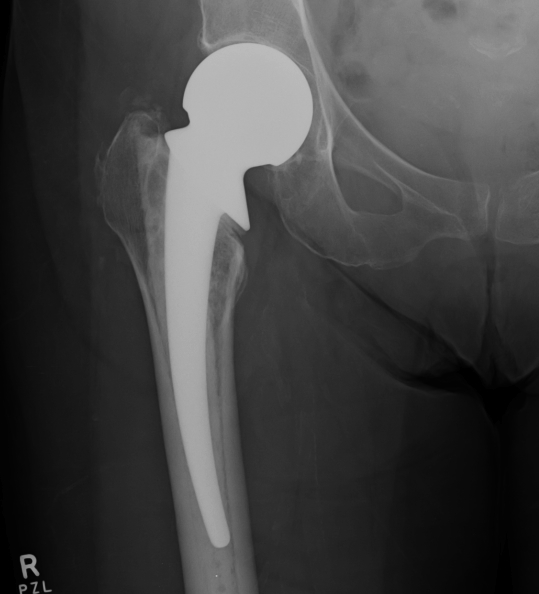

Unipolar

- single articulation between prosthesis and acetabulum

Unipolar monoblock

- Austin Moore press fit

- Thompson cemented

- no offset options

Austin Moore Thompson

Modular unipolar

Based on standard THR concepts

- alternative offset options

- neck length options

- cemented or uncemented